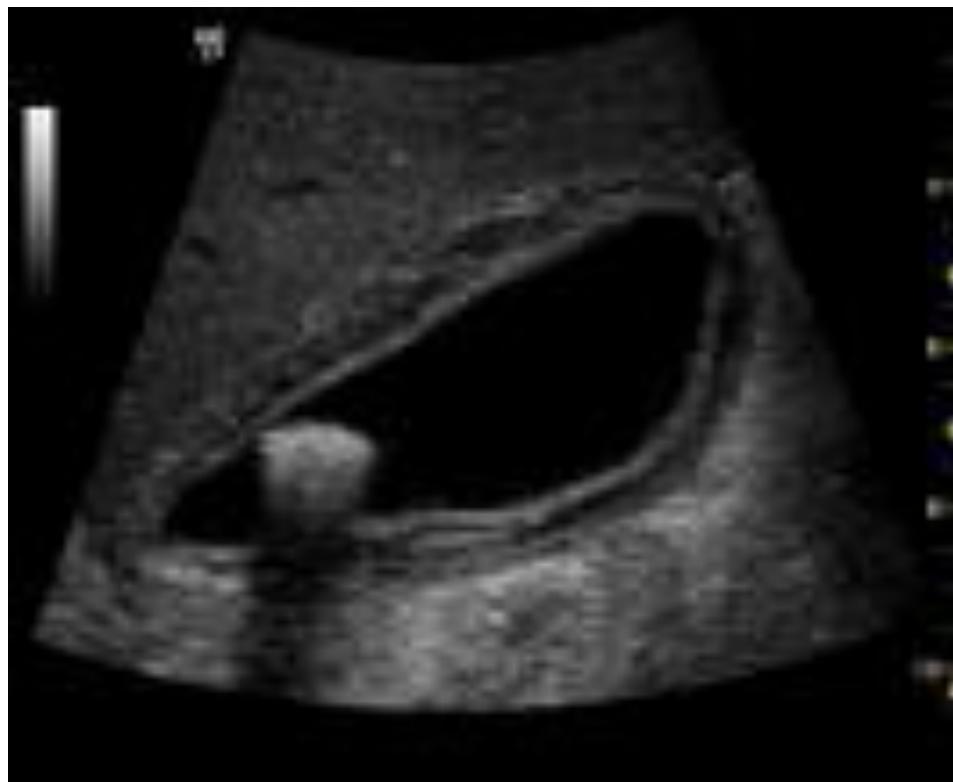

FAST / eFAST Ultrasound

- Modality: Focused Assessment with Sonography in Trauma (FAST).

- Standard 4 Views:

- RUQ (Morisonโs Pouch): Hepatorenal recess.

- LUQ: Splenorenal recess.

- Pelvic (Pouch of Douglas): Suprapubic window.

- Pericardial: Subxiphoid window.

- eFAST: Includes the pleura to check for pneumothorax/hemothorax.

- Positive Finding: Anechoic (black) fluid collection indicating blood in a trauma patient.